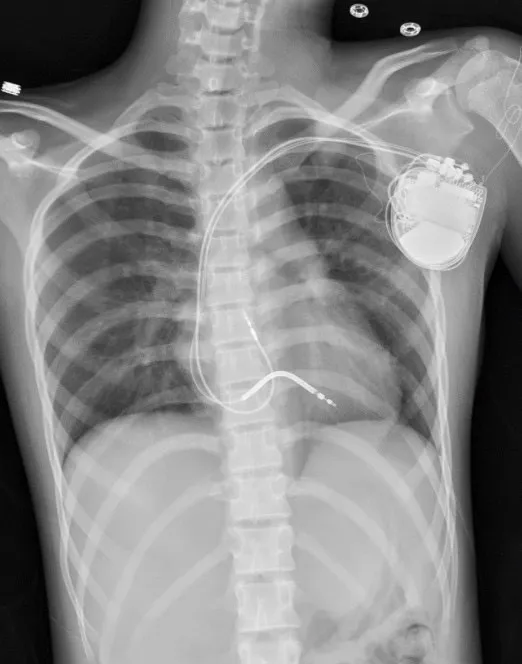

中醫大兒醫醫療團隊替小涵安裝體內去顫器,確保突發心室頻脈時,可立即電擊搶救。中醫大附醫提供